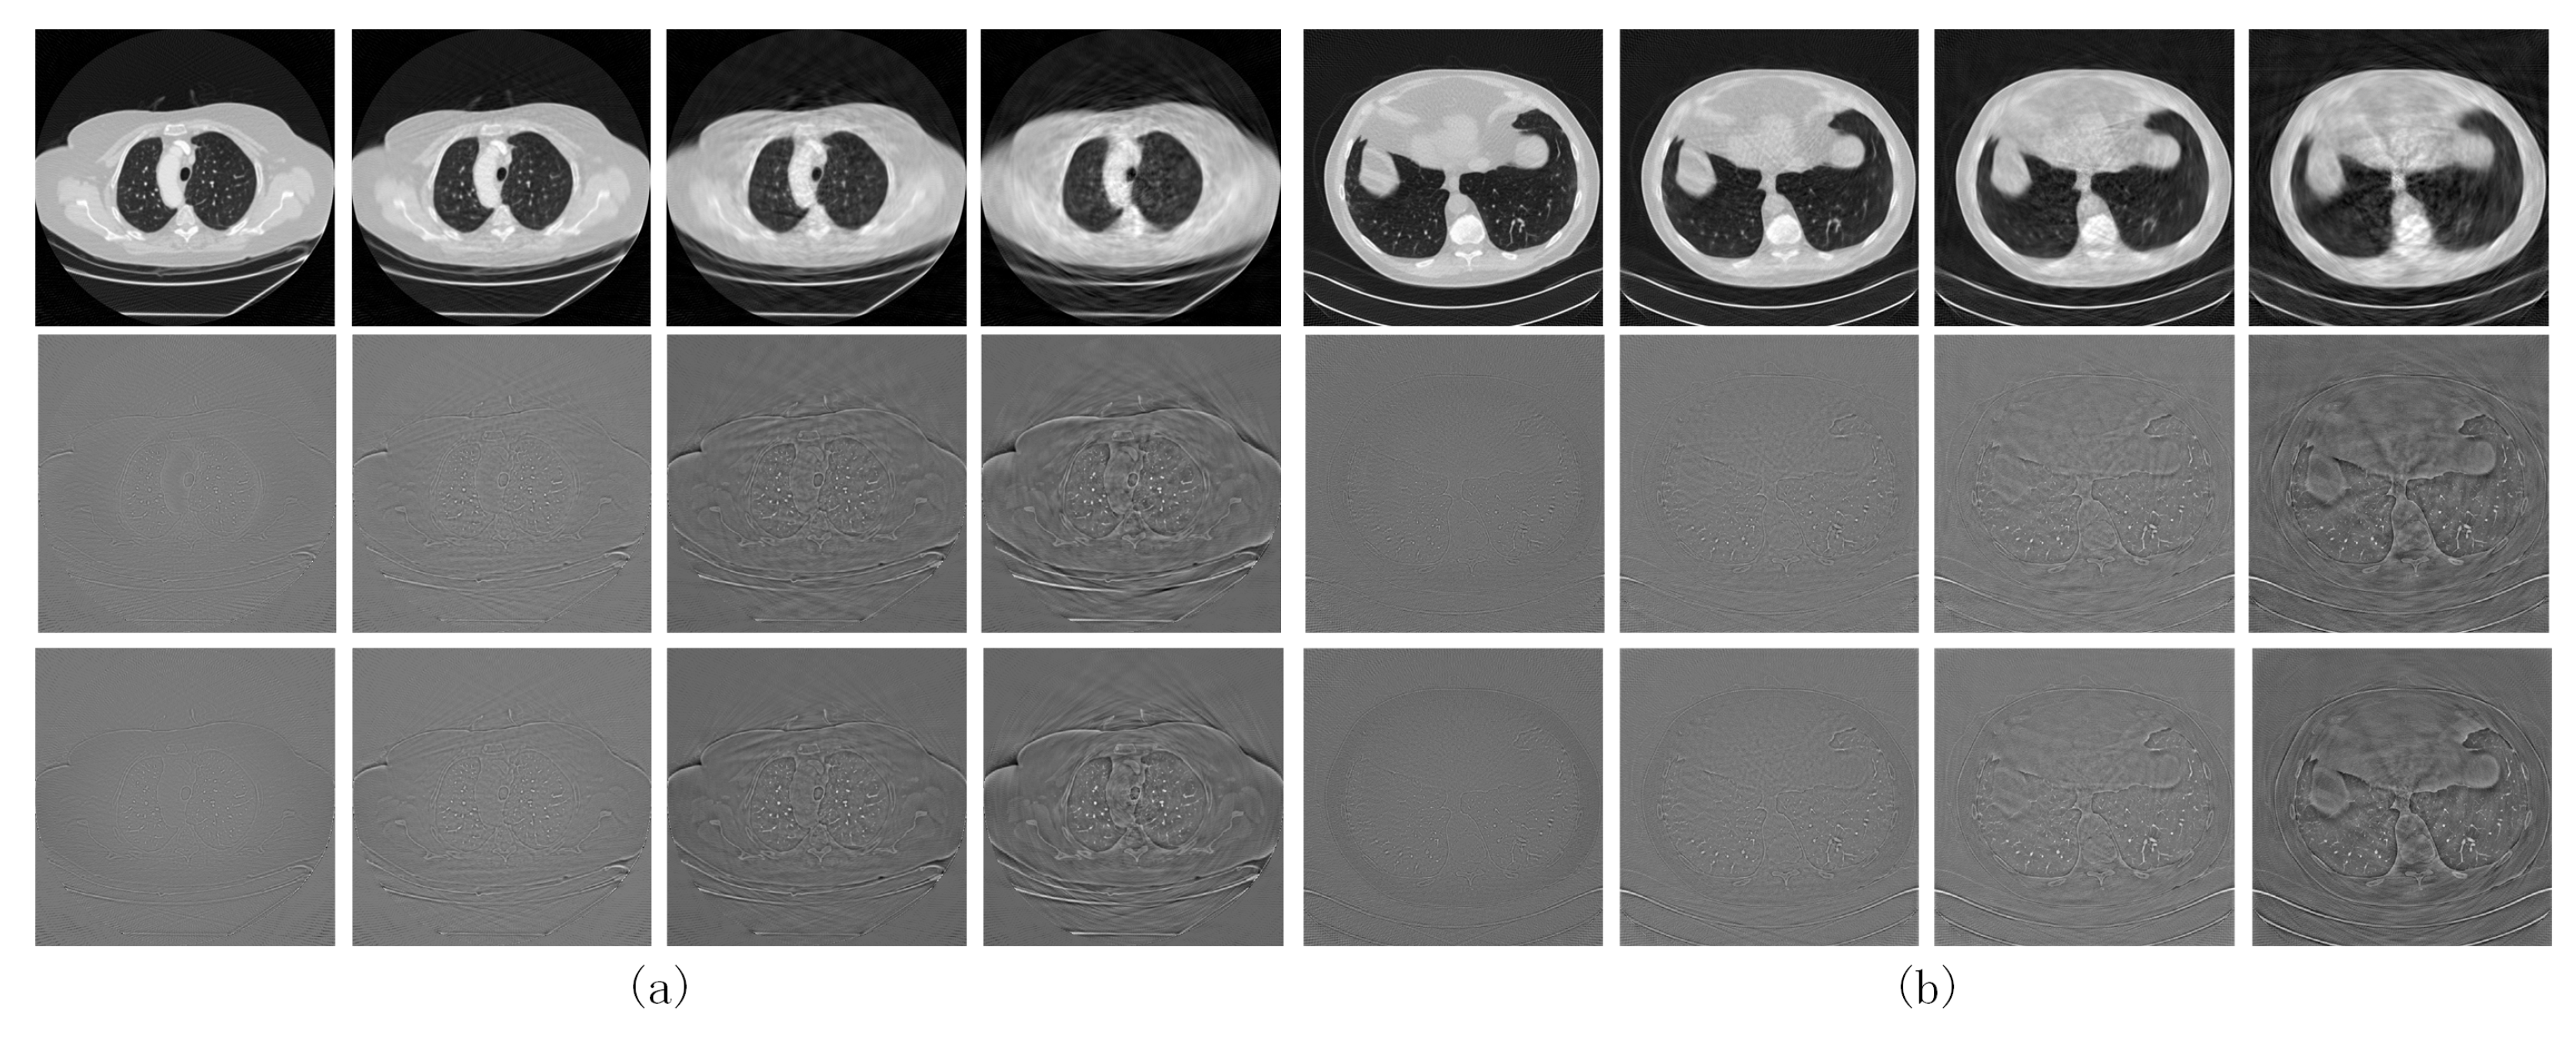

The reconstruction results obtained by training the sinogram domain network using the image domain loss were also investigated and compared with those obtained using the sinogram domain loss .

The first two rows in Figure 5 show the reconstructed images obtained from our network trained with and their absolute difference from the full-dose CT results, respectively.

Figure 5.

CT images obtained by training the proposed network using the image domain loss () on (a) the LIDC-IDRI dataset and (b) the AAPM dataset. The first and second rows show the reconstructed image obtained by training with and its difference with the label, respectively. The third row shows the difference between the reconstructed image obtained by and the label.

The counterparts obtained via training with are shown in the last rows of Figure 4 and Figure 5, respectively. Comparing the quantized difference images shows that the image domain loss is better than the sinogram domain loss at lower sparse levels. As analyzed in Section 2.3, setting back the loss function to the image domain can to some extent coordinate the reconstruction error of the FBP module itself using the sinogram domain interpolation network, resulting in better CT reconstructed images. However, for higher sparsity levels, the results corresponding to image and sinogram domain losses tend to be consistent. To quantitatively evaluate the two loss functions, the PSNR- and SSIM-S (where S denotes the sparsity levels) curves for the CT images reconstructed by the proposed network trained with the two loss functions are compared in Figure 6a,b. The corresponding PSNR-S curves of the predicted sinogram are also compared in Figure 6c.